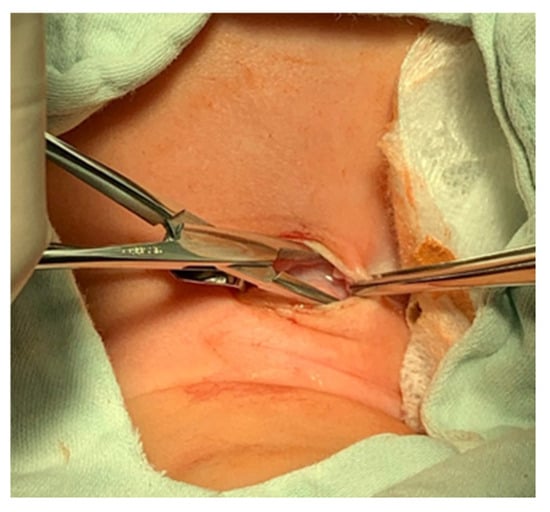

- The resulting triangular skin flaps are dissected from the underlying tissues using a dissecting scissors (Figure 12).

- The subcutaneous adipose tissue covering the elongated neck muscles is removed (Figure 13).